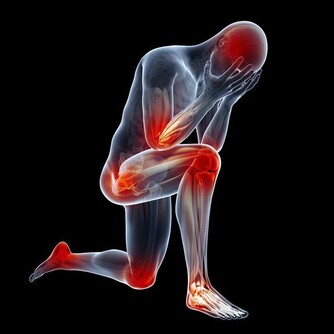

肺部,掌管我們身體中氧氣的輸入和輸出。肺部的健康對我們生命活動都起到著很重要的作用。但是,很多人每天能卻都在做著傷害肺部健康的事情。那就是抽煙。

據研究顯示,抽煙是當今社會導致肺癌的罪魁禍首之一。約40%的慢性阻塞性肺病由吸煙直接引起。吸煙指數(每天吸菸支數×菸齡)大於400者,患肺癌的機率將升高7倍之多。而對於長期吸二手煙的人來說,患肺癌的機率將會提高25%以上。